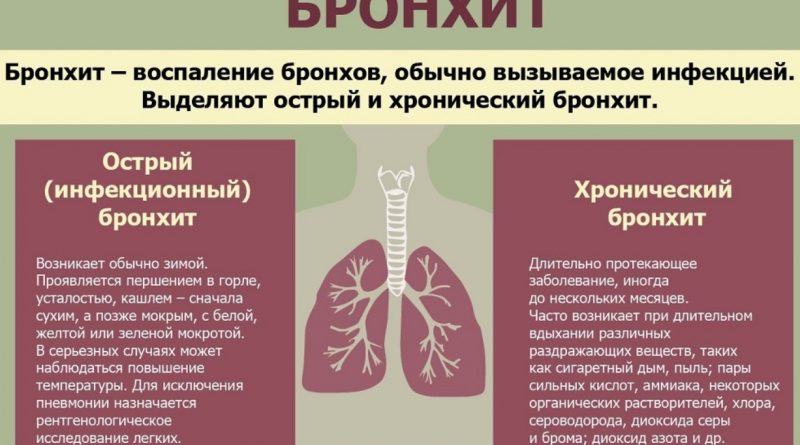

Бронхит – заболевание дыхательной системы, при котором происходят воспалительные процессы в бронхиальном дереве. Одни из основных признаков болезни — значительное повышение температуры тела и кашель. Но иногда бывает и бессимптомное течение бронхита. Как диагностировать его в этом случае и какие методы лечения использовать, узнайте далее.

Виды бронхита без температуры

Существует несколько форм бронхита, при которых температура тела чаще всего держится в пределах нормы. К ним относятся:

Острый бронхит, проявляющийся как осложнение других болезней дыхательной системы, всегда сопровождается повышением температуры тела.